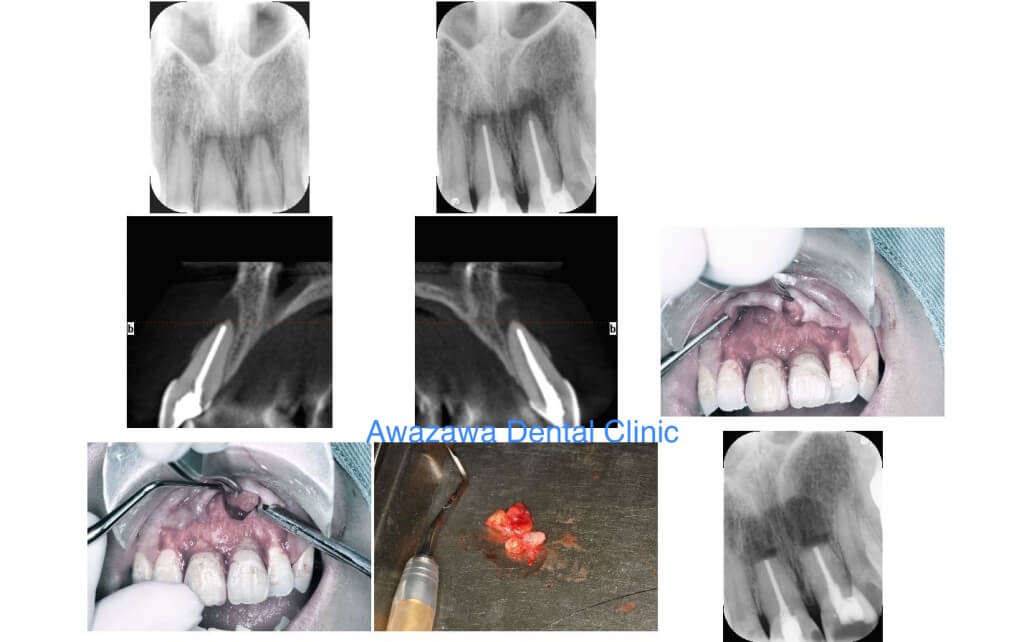

歯根端切除手術

Case.1

CT像で下顎の前歯の根の先に嚢胞の陰が認められます。嚢胞と共に、感染した歯根の先端部を切断し摘出する事で歯を抜歯する事なく処置する事ができます。

Case.2

不適合なブリッジが装着され、CT画像で根端部の嚢胞が認められます。歯内療法後に歯根端切除及び嚢胞摘出処置を行い、セラミックブリッジによる補綴処置をいたしました。